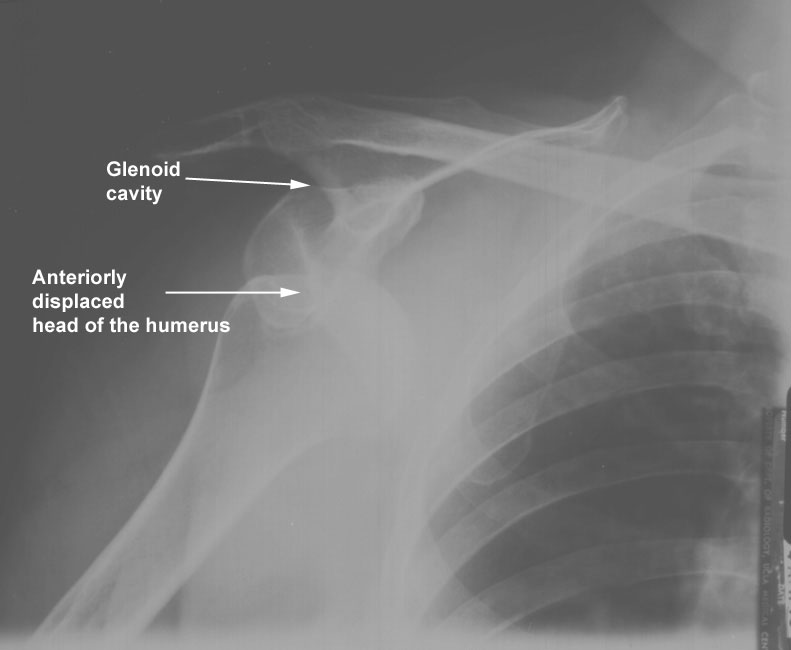

The goalkeeper in a soccer match fell on his outstretched left arm. He felt an immediate pain in the shoulder region and was unable to move his arm. At the hospital the arm was abducted and the deltoid muscle looked flat or hollow. The injured arm looked "too long", and there was intense pain on attempting to move the arm. A plain radiograph of the region showed that the humeral head was lying below the glenoid labrum and that there was no fracture of the humerus. The diagnosis was an anterior dislocation of the shoulder, and the orthopedic surgeon recommended Kocher's maneuver for management.

1. Why did the deltoid appear flat and hollow?

Because of the downward displacement of the humeral head.

The axillary nerve and the posterior humeral circumflex artery. Axillary nerve injury may be assessed clinically by examining skin sensation over the deltoid region, which is supplied by the upper lateral brachial cutaneous branch (C5) of the axillary nerve. Examining the deltoid will be difficult in dislocated shoulders.

3. What is the anatomical principle in reducing a dislocated shoulder?

The elbow must be flexed under traction, humerus laterally rotated, adducted and then rotated medially. An X-ray is taken to ensure proper reduction, and axillary nerve function is assessed by asking the patient to abduct the shoulder.